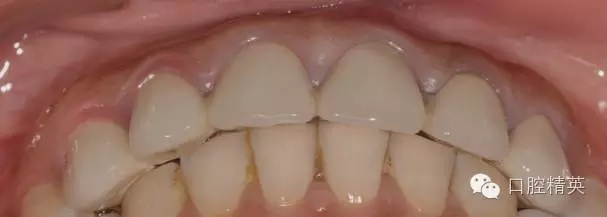

患者發(fā)F音以及下嘴唇干濕線的位置

修復(fù)體完成口內(nèi)照片